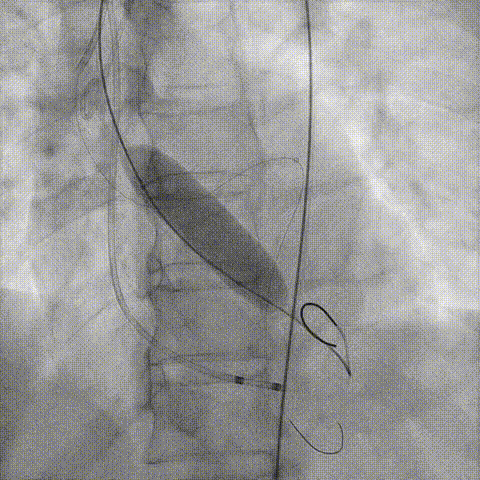

预置Telescope™导引延长导管及导丝保护左冠,

18mm球囊预扩张再次评估冠脉闭塞风险。

Telescope™+Runthrough

18mm*40mm 预扩张

预埋 Resolute Integrity 3.5*26mm

再次评估左冠开口

第一次释放

再次评估左冠开口,考虑调整瓣膜深度

回收后调整深度,再次释放

评估左冠开口

左冠开口切线位造影

决定左冠烟囱支架保护冠脉

调整支架位置

释放冠脉支架

释放瓣膜

造影评估

支架内后扩张